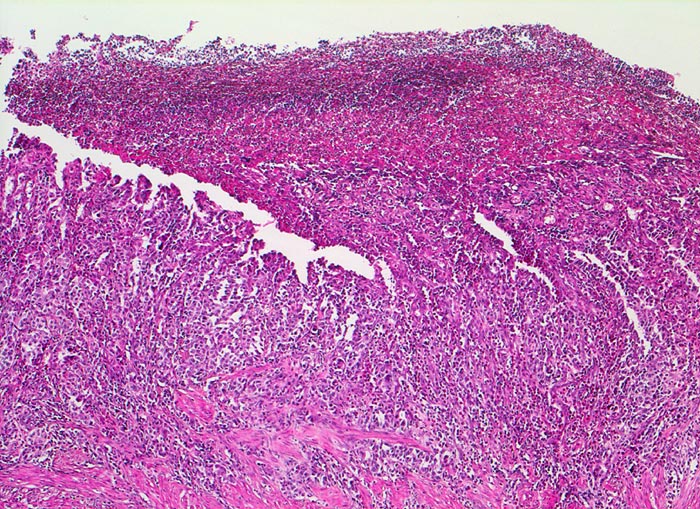

• Am unteren Ende des Präparates Antrummukosa mit mässiggradiger chronischer, geringgradig aktiver Gastritis und ausgedehnter intestinaler Metaplasie (Becherzellen).

• Weiter oben Invasion der Magenschleimhaut durch ein teils solides, teils drüsenbildendes Adenokarzinom mit stark atypischen Tumorzellen.

• Fokale Erosion des Karzinoms bedeckt von fibrinoleukozytärer Membran.

• Tumorinfiltration der Submukosa an der oberen Präparathälfte.

• Der invasive Karzinomanteil zeigt teilweise muzinöse Differenzierung (teils siegelringzellige Tumorzellen schwimmen in extrazellulären Schleimseen).

• Tumorfreie Lamina muscularis propria.